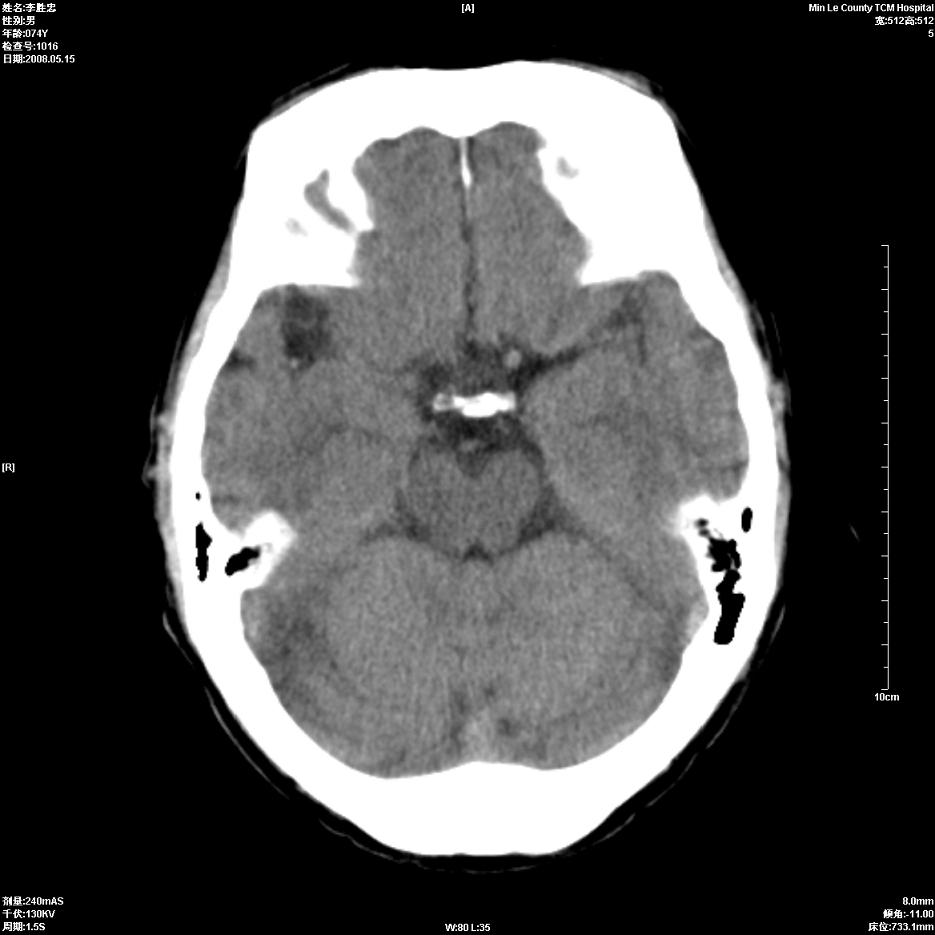

以下是引用hhcckk在2008-5-30 14:26:00的发言:[br]病灶跨中线,有占位效应,强化不明显,考虑胼胝体区低级别的星形细胞瘤可能性大,建议mr检查